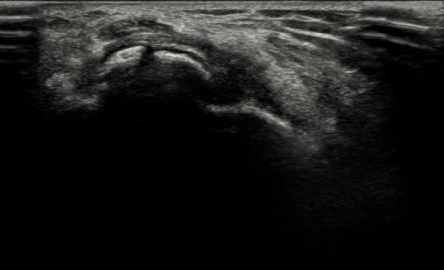

수술 전

2022.06.08